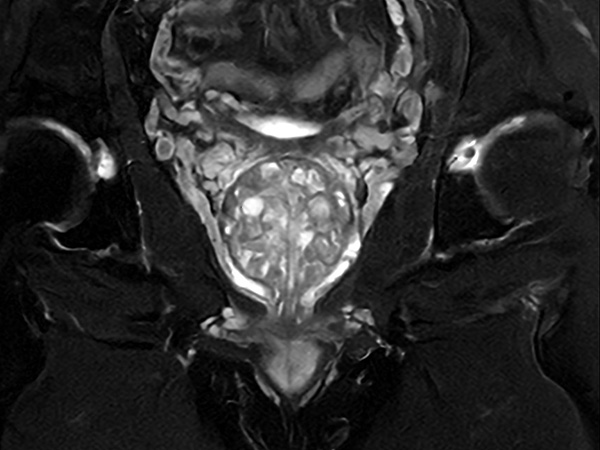

Fast Prostate imaging with SmartSpeed Precise

Kumamoto Chuo Hospital Japan